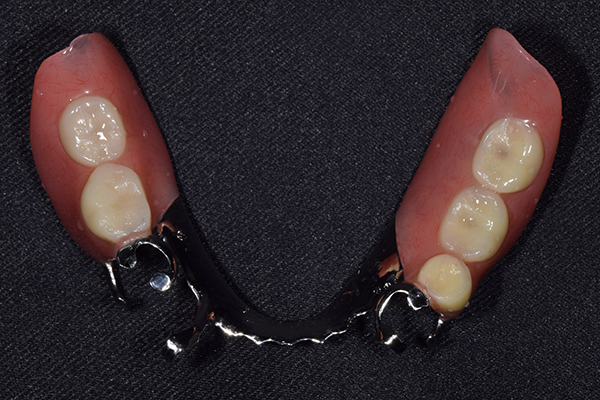

ケース1(自費の部分入れ歯)

前歯が折れて当院にいらっしゃいました。 過去に下の入れ歯を作ったが、合わなくなってずっと入れ歯をいれていらっしゃらない患者様でした。 これは奥歯で噛むことができないため、前歯で噛むことを繰り返したために、負担に耐えられなくなった前歯が折れてかぶせ物ごと 外れてしまったのだと考えられます。 痛くない、違和感の少ない、下の入れ歯を作ることがこの方のゴールであると考えられました。

金属を使用して、薄く違和感が少ない入れ歯が完成しました。 また、見た目にも気を使い、バネが見えにくい様な構造にしました。

義歯は下顎で、しっかり噛めること、違和感の少ないものという希望があったため、なるべく入れ歯を薄く作成するために金属をしようした義歯とした。

また、見た目もあまり義歯が目立たない様に、バネの部分を見えにくいように作成した。